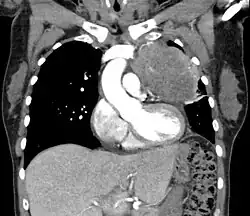

Thymic carcinoma seen on CT.

Diagnosis of thymic carcinoma is based on a combination of clinical, radiologic, and biopsy findings. Most early cases are asymptomatic and found incidentally on chest radiographs as a mass in the anterior mediastinum. Further evaluation consists of additional imaging, such as CT, MRI, and PET, and tumor biopsy, which is the gold standard and provides the definitive diagnosis.[5] Biopsy may be done prior to surgery by fine needle aspiration or during the surgery with concomitant evaluation by the pathologist.[8] Other carcinomas with malignant spread to the thymus are on the differential diagnosis and must be excluded, as they may appear similar to thymic carcinoma on histopathological examination. [3]